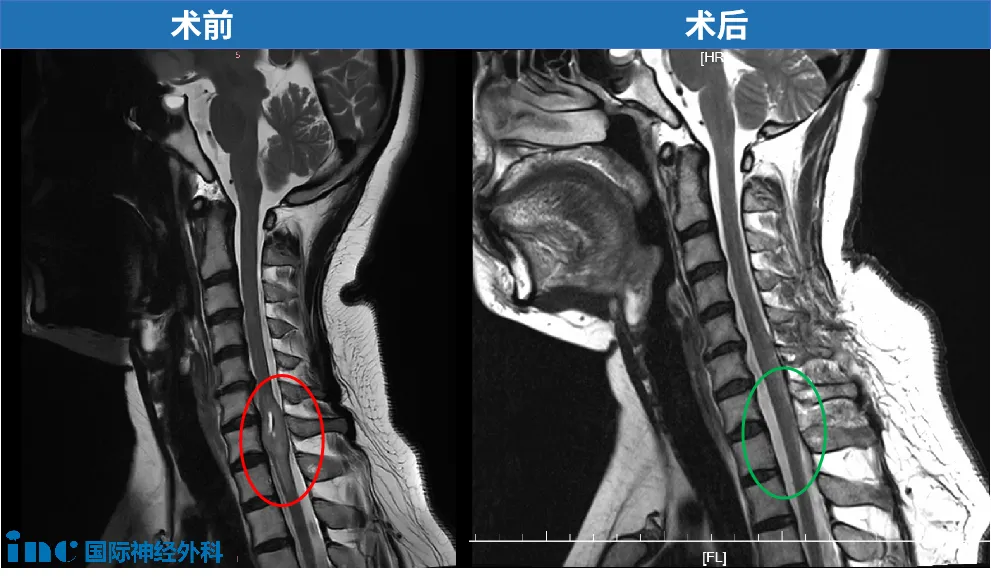

那位骨科医生经验丰富,听完我的描述,他表情严肃地建议我:“你需要拍一个核磁共振(MRI)。”我听从了建议。结果出来后,医生看着片子的表情让我心头一紧。他告诉我,我的脊髓里可能长了个肿瘤。那一刻,我完全懵了。肿瘤?我从没想过会这么严重,更没想到它会压迫那么多重要的神经。

为了确诊,我当天又做了增强核磁。中午12点,报告就出来了,我拿到了那个陌生的疾病名称:脊髓髓内肿瘤。从那一刻起,我的人生被彻底改变了。

肿瘤顺利全切

巴教授中国学术交流期间,我的手术如期进行,由巴教授主刀。术后我在ICU住了一晚。让我无比感动的是,周六早上,巴教授竟然穿着隔离服,专门到ICU病床前来看我。他检查了我的腿部活动,一直鼓励我:“你很棒,勇气很大。”这句简单的鼓励,在那个时刻给了我无穷的力量。

那天晚上,我几乎没睡,一直在尝试活动我的脚趾,看着脚尖一点点抬高。一种强烈的感觉涌上心头:我终于和那个肿瘤剥离了,我是胜利的。